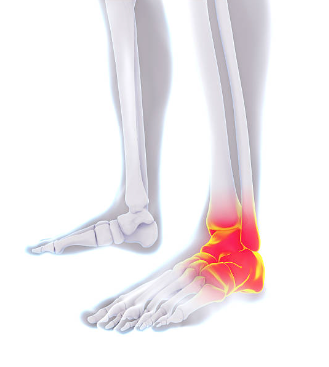

2. 관절염과 관절 염증

관절염은 관절의 염증을 포함하는 상태입니다. 이는 발목을 포함한 몸의 어떤 관절이든 영향을 미칠 수 있습니다. 발목에서 볼 수 있는 두 가지 일반적인 관절염 유형은 다음과 같습니다:

골관절염 (Osteoarthritis)

골관절염은 주로 나이가 들면서 연골이 점차 붕괴되는 과정과 관련이 있습니다. 발목에서는 연골이 파괴되면서 통증, 경직 및 기동성 감소가 발생할 수 있습니다.